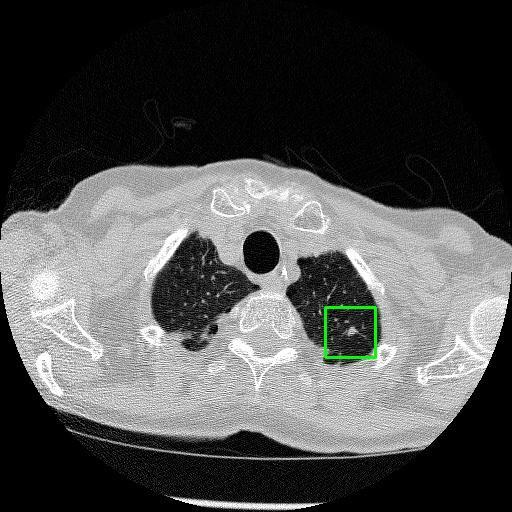

We developed an AI-based system using deep learning models for analyzing lung CT scans to detect and classify pulmonary nodules. We chose the YOLOv11 architecture for its enhanced object detection capability and adapted it specifically for medical imaging, incorporating pixel-level precision and severity classification.

Classification into three severity levels with colored bounding boxes.

Designed a severity classification system that categorizes nodules into null, moderate, and severe using colored bounding boxes, assisting in rapid clinical decision-making.